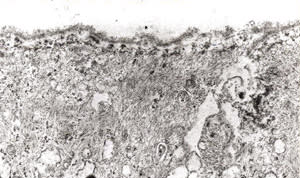

LASEK as described by Camellin begins with the creation of a corneal epithelial sheet by applying ethanol for 20 seconds. The sheet is "rolled up" using a spatula. Stromal ablation is then applied. After ablation, the epithelial sheet is repositioned over the treated area. |

Now that interest in surface ablation is once again increasing with the introduction of wavefront-guided ablation, the new frontier seems to be an automated LASEK procedure performed without alcohol. Dr Ioannis Pallikaris has developed a new keratome to perform a procedure that he calls epi-LASIK. This instrument uses a flexible plastic separator with a dull edge. No applanation of the cornea is necessary, and the separator slides under the epithelium along the path of least resistance, leaving the basement membrane intact. The instrument is designed not to engage stroma. Studies performed in pig eyes verified that this keratome left a smooth surface. A recent report by Dr. Pallikaris on 34 myopic eyes of 17 patients treated with epi-LASIK stated that epithelial separation was achieved in 100% of cases. The post-op regimen included bandage contact lenses, anti-infectives, steroids, and nonsteroidal anti-inflammatories, but no "comfort drops" of dilute anesthetics. Only one of the 17 patients reported moderate post-op pain, and this was due to a tight bandage contact lens. One advantage of this instrument and technique may be that it cleaves the basement membrane underneath the laminas lucida and densa, at the level where it contacts Bowman's layer. Human histopathology studies have shown that epi-LASIK leaves the basal cells and their hemidesmosomes (which act as mechanical "fasteners") attached to the epithelium, which should improve the reattachment of the epithelium. Alcohol splits the basement membrane. Since the adherence of the basement membrane to the basal layer of the epithelium is significant for the viability of an epithelial sheet, we assume that the cleavage plane of the mechanical epi-LASIK separation may be superior.